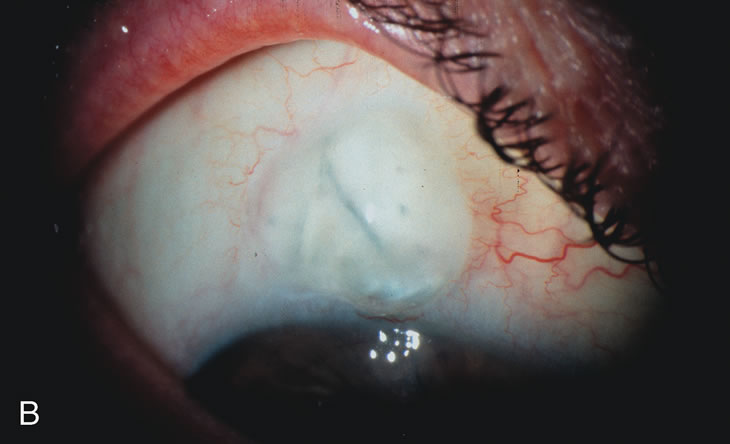

Fig. 1. The anatomic advantage of small incision cataract surgery for the glaucoma patient. A. Long-term bleb function with a large cataract incision is difficult to achieve with either ECCE-trabeculectomy or trabeculectomy followed later by ECCE. This bleb failed to form sufficiently when combined with large incision ECCE. The inflammation, bleeding, and long-term wound healing with stimulation of fibroblasts associated with this technique are more likely to cause bleb failure. In addition, the increased iris manipulation necessary to deliver the nucleus and subsequent iris repair adds to the long-term breakdown of the blood aqueous barrier. B and C. Two-site phacotrabeculectomy has the advantage of small incision cataract surgery combined with separate site trabeculectomy. The incision size is one third the size of the standard ECCE. The inflammation is less severe, and cataract wound healing is confined to the temporal area. Visual rehabilitation with phacoemulsification and foldable IOL is much faster. Phacoemulsification allows successful lens extraction even in the unfriendly environment of a smaller pupil compared with ECCE. The trabeculectomy is performed in an entirely different site, well away from the wound healing associated with temporal phacoemulsification. The likelihood of this filter functioning long-term is greater than with ECCE-trabeculectomy. D. The surgeon also has the option of single-site phacotrabeculectomy with foldable IOL. Both the lens extraction and trabeculectomy are performed through one small 3.5-mm limbal incision.

Fig. 3. Partial bleb failure following clear corneal phacoemulsification with foldable IOL. A. Preoperative bleb appearance prior to temporal lens extraction. Preoperative IOP was 12 mm Hg on no antiglaucoma medications. Time from 5-FU trabeculectomy surgery to lens extraction was one year. B. Bleb appearance 2 months after clear corneal cataract surgery with topical anesthesia. Following lens extraction, increased vascularity was noted along with decreased size of the filtering bleb. IOP increased to 20 mm Hg as early as 2 weeks after surgery, necessitating topical antiglaucoma therapy. C. High magnification view of bleb before lens extraction demonstrates diffuse pale bleb. D. High magnification view of bleb 2 months after surgery. There are vessels surrounding the nasal side of the bleb and the overall bleb size is smaller.